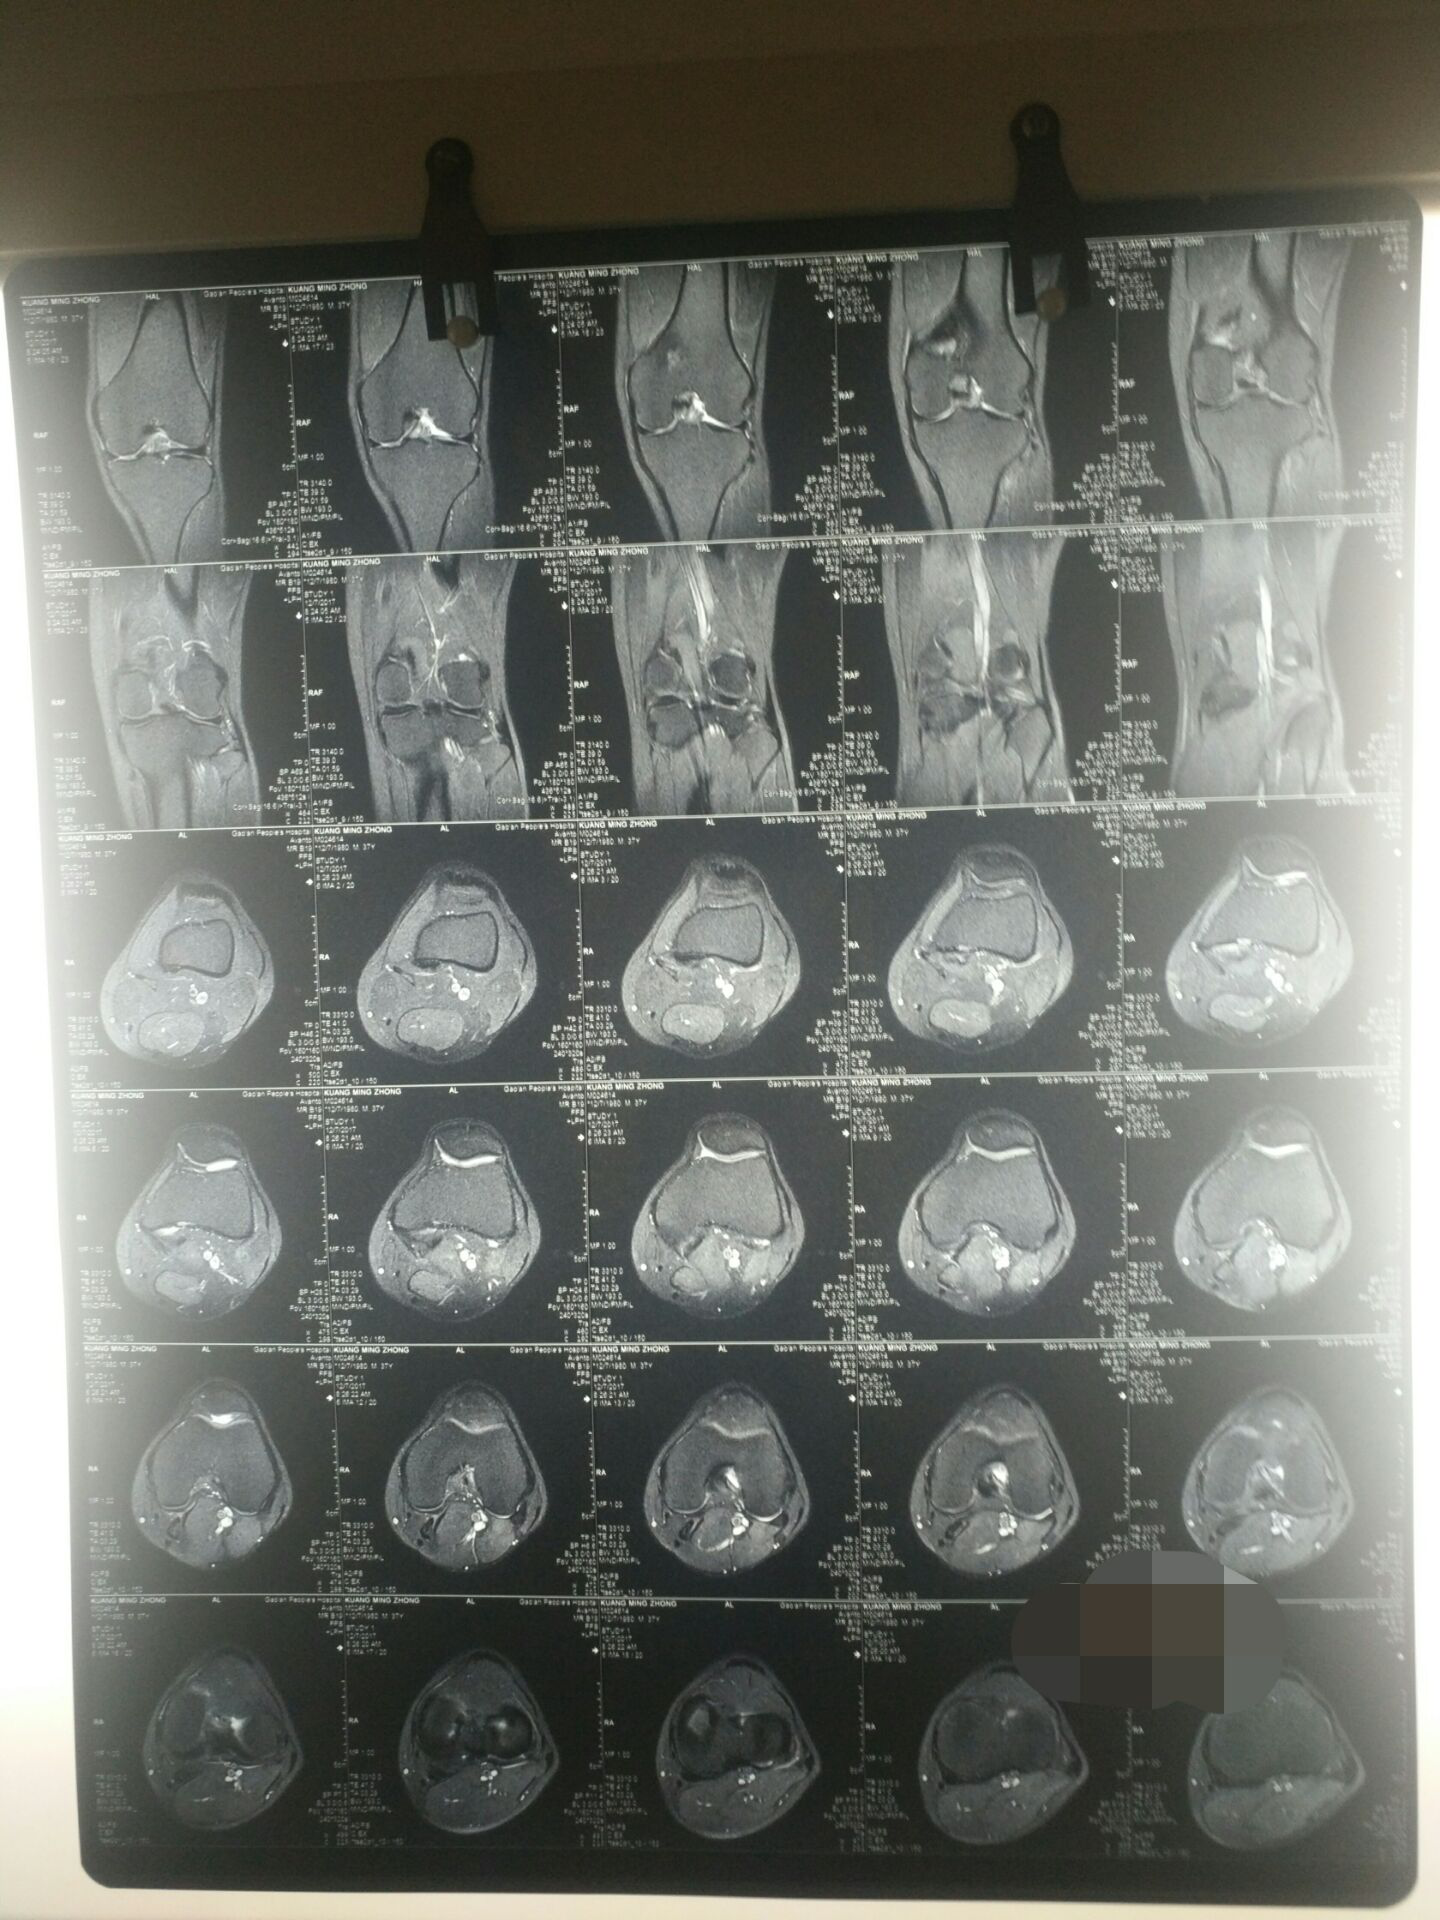

3、复阅高安市人民医院DR(550459、559863等):左股骨大转子骨折。

2、左髋部压痛,左髋关节活动障碍。左髋关节活动范围:前屈75°后伸10°外展35°内收10°外旋30°内旋30°,左髋关节活动功能丧失33.3%(祥见附件图片)。